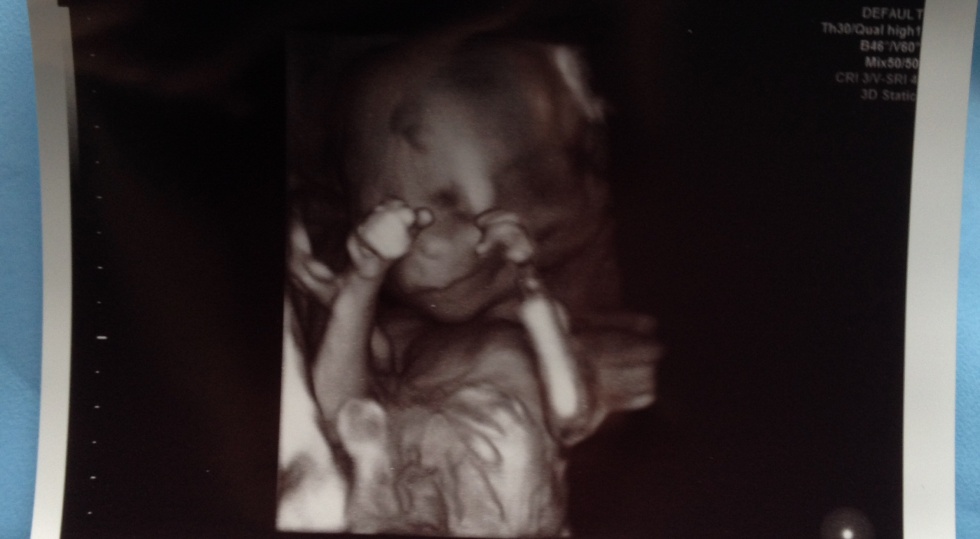

v. 16 (fick en gratis en extrabild i 3 D, en aning creapy men sjukt häftigt att se :D).